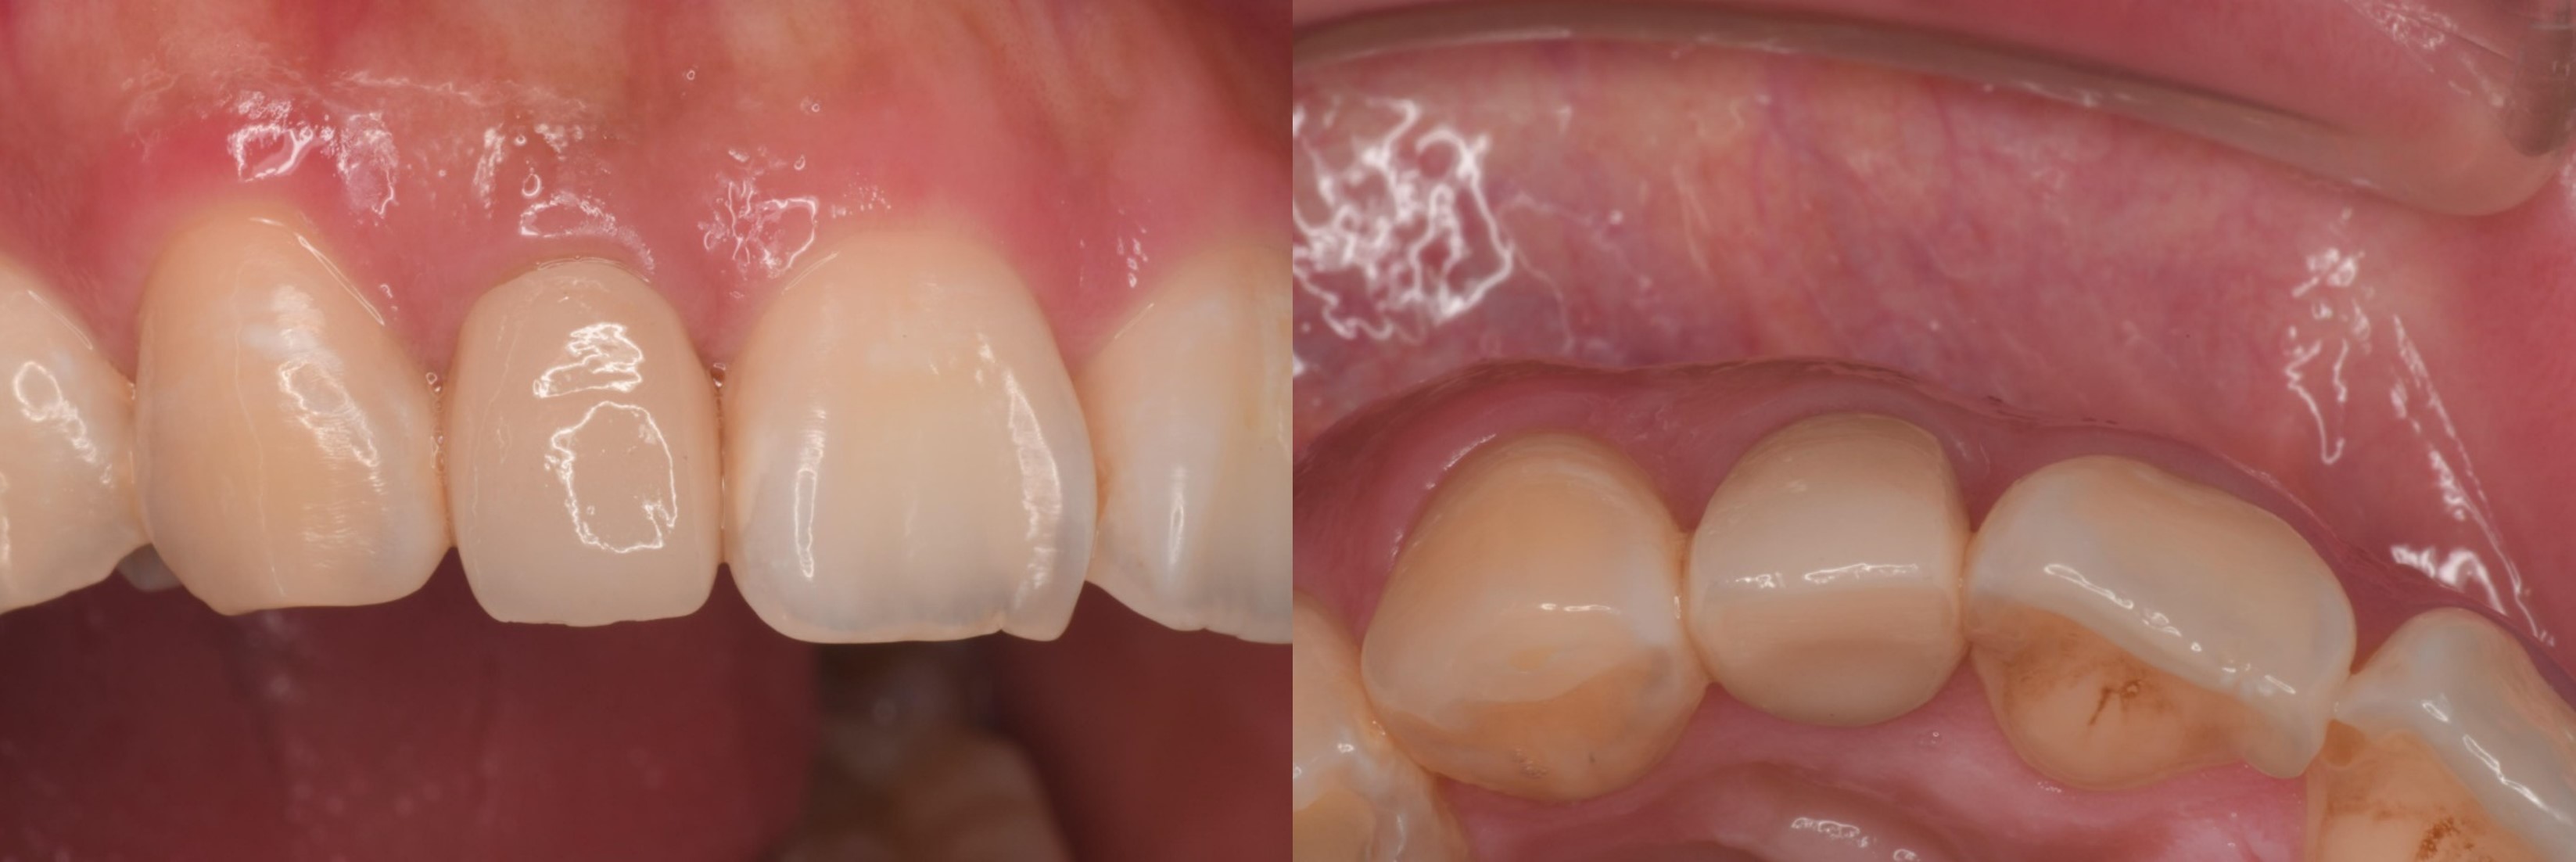

治療前,牙齦腫脹